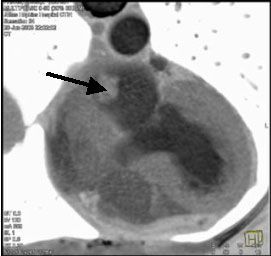

![]() |

| Рис.28. МСКТ сердца, миксома левого предсердия (стрелка) |

Другое направление для проведение 64 МСКТ - это диагностика новообразований сердца, инфильтрации миокарда при амилоидозе, саркоидозе [31,53] (рис № 28). МСКТ за считанные минуты позволит с высокой степенью достоверности уточнить локализацию поражения сердца, а также даст дополнительную возможность изучить состояние кровообращения в венечных артериях сердца, провести оценку перикардиальных структур, клапанов.